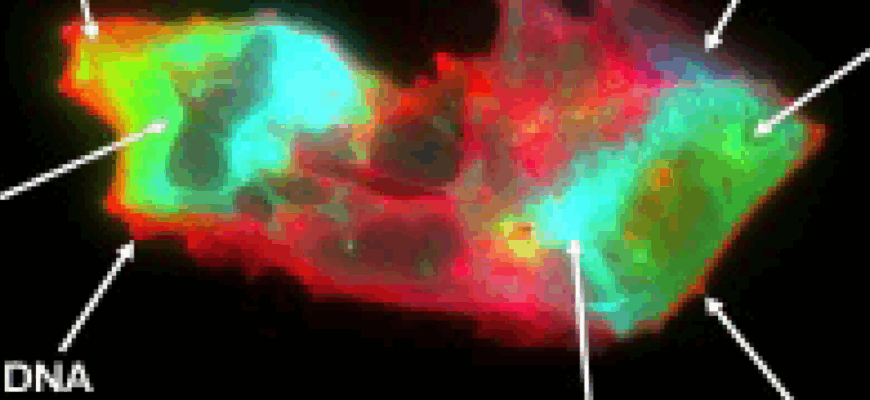

Команди Преторіус і Тьєррі провели комплексний аналіз плазми пацієнтів за допомогою флуоресцентної мікроскопії та проточкової цитометрії з візуалізацією. NETs оцінювали за наявністю білкових маркерів і циркулюючої ДНК. Виявилося, що структурна взаємодія між NETs і мікотромбами — значно вища у хворих на Long COVID, ніж у здорових осіб. “Це вказує на фізіологічну взаємозалежність, яка в умовах дисбалансу стає патогенною,” — наголошує д-р Тьєррі.